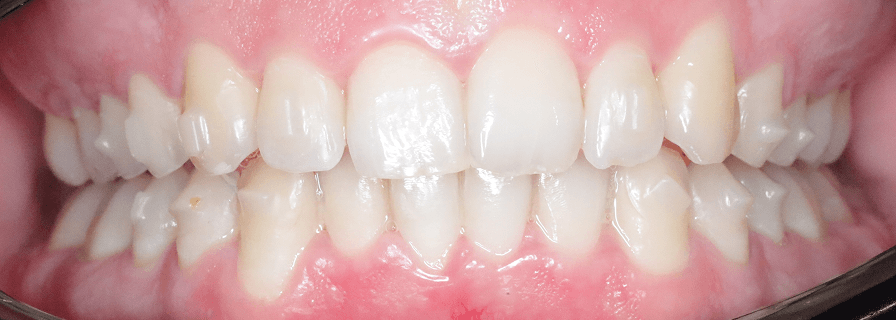

Corectarea Supraacoperirilor și Înghesuirilor Dentare

Pentru acest pacient de 20 de ani am rezolvat problemele complexe de înghesuire și supraacoperire folosind aparat fix bimaxilar. Evaluăm fiecare caz individual pentru a alege cea mai eficientă metodă de tratament. Rezultatele au fost obținute în aproximativ 1 an.